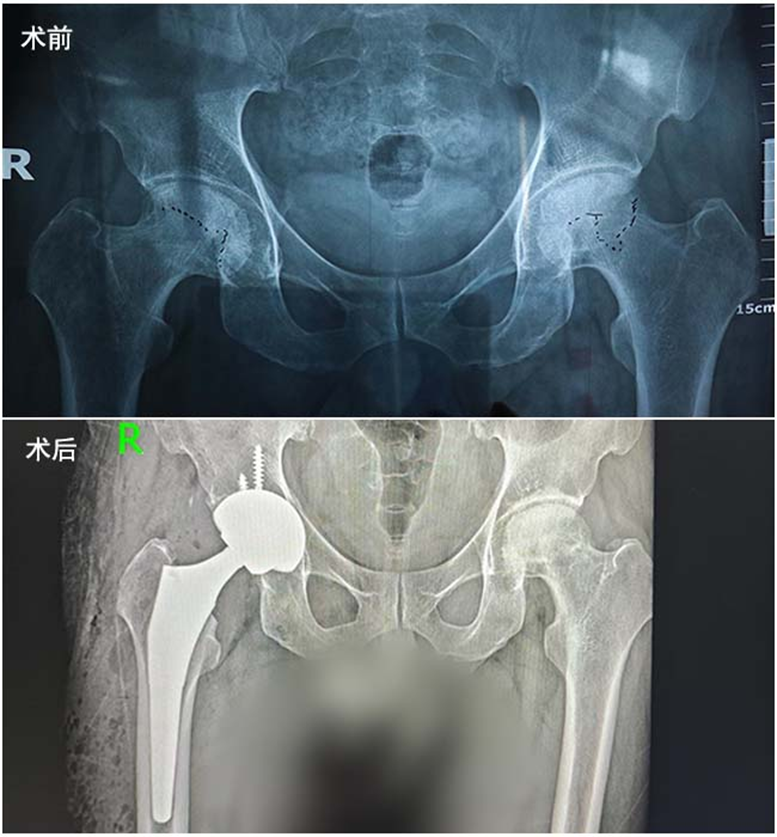

今年45岁的王先生,曾因误诊为腰椎疾病,错失了最佳治疗时机,延误病情长达一年多。当最终确诊时,其股骨头坏死已发展至末期,髋关节疼痛难忍、活动受限,正常行走都成了奢望。为了彻底治好病,重新找回行走能力,王先生下定决心接受关节置换手术,但面对这类大型手术,他格外慎重,四处打听、多方对比,最终将目光锁定在前侧入路(DAA入路)微创置换技术上。“我咨询了很多做过同类手术的病友,大家都推荐前侧入路,说这种方式创伤小、恢复快,术后遭罪少,舒适度高。”王先生回忆道。

2026年4月,怀揣着康复的希望,王先生从黑龙江大庆跨越千里,专程来到专注于骨关节疾病诊疗的济南关节外科医院。据悉,该院在DAA入路微创髋关节置换手术领域深耕多年,积累了丰富的临床经验,手术团队技术娴熟、配合默契,已帮助众多股骨头坏死、髋关节病变患者重获健康。入院后,医院为王先生开展了全面、细致的术前检查,结合其病情、身体状况等综合评估,确认他完全符合DAA(前侧入路)微创髋关节置换手术指征,随即制定了个性化的手术方案。

在完善术前准备后,医院手术团队默契协作,顺利为王先生完成了DAA入路微创髋关节置换手术。术后,王先生的感受正如病友所说,完全超出预期:康复过程十分舒适,无明显剧烈疼痛感,恢复速度远超想象——术后不到24小时,他就能顺利下地行走,自主完成上厕所、打水等日常活动,基本不影响正常生活,这让他欣喜不已。

济南关节外科医院肖国文院长介绍,DAA入路(前侧入路)是全髋关节置换手术的一种微创入路方式,其通过人体自然存在的肌间隙进入手术区域,无需切断任何肌肉、血管和神经,从根源上减少了手术创伤。与传统手术入路相比,DAA入路具有手术切口小(不到8cm),创伤小、出血少;术后疼痛轻微,患者舒适度高;脱位率极低,关节活动度恢复更好等优势。